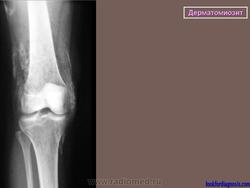

Морфологическая картина включает воспалительные инфильтраты в межмышечной соединительной ткани и вокруг мелких сосудов, дистрофию и некроз мышечных волокон. Воспалительные инфильтраты состоят преимущественно из мононуклеаров, плазматических клеток, эозинофилов. При длительном течении заболевания могут быть обнаружены фиброз и кальциноз. На аутопсии иногда наблюдают распространенный васкулит. При морфологическом исследовании пораженных участков кожи выявляют лишь неспецифические воспалительные изменения.

Подострое течение заболевания отличается цикличностью, с постепенным и неуклонным нарастанием симптомов. Этот вариант близок к острому и без лечения также заканчивается летально или приводит к тяжелому кальцинозу, контрактурам, обрекающим больных на постельный режим.

2) скелетно-мышечный синдром (генерализованное поражение поперечнополосатых мышц); на ранних этапах — нарастающая слабость мышц плечевого пояса и проксимальных отделов нижних конечностей (при отсутствии симптомов полиневрита), миалгии, особенно при движении, надавливании, отеки мышц; позже — миосклероз, контрактуры, атрофии, как правило, проксимальных отделов конечностей;